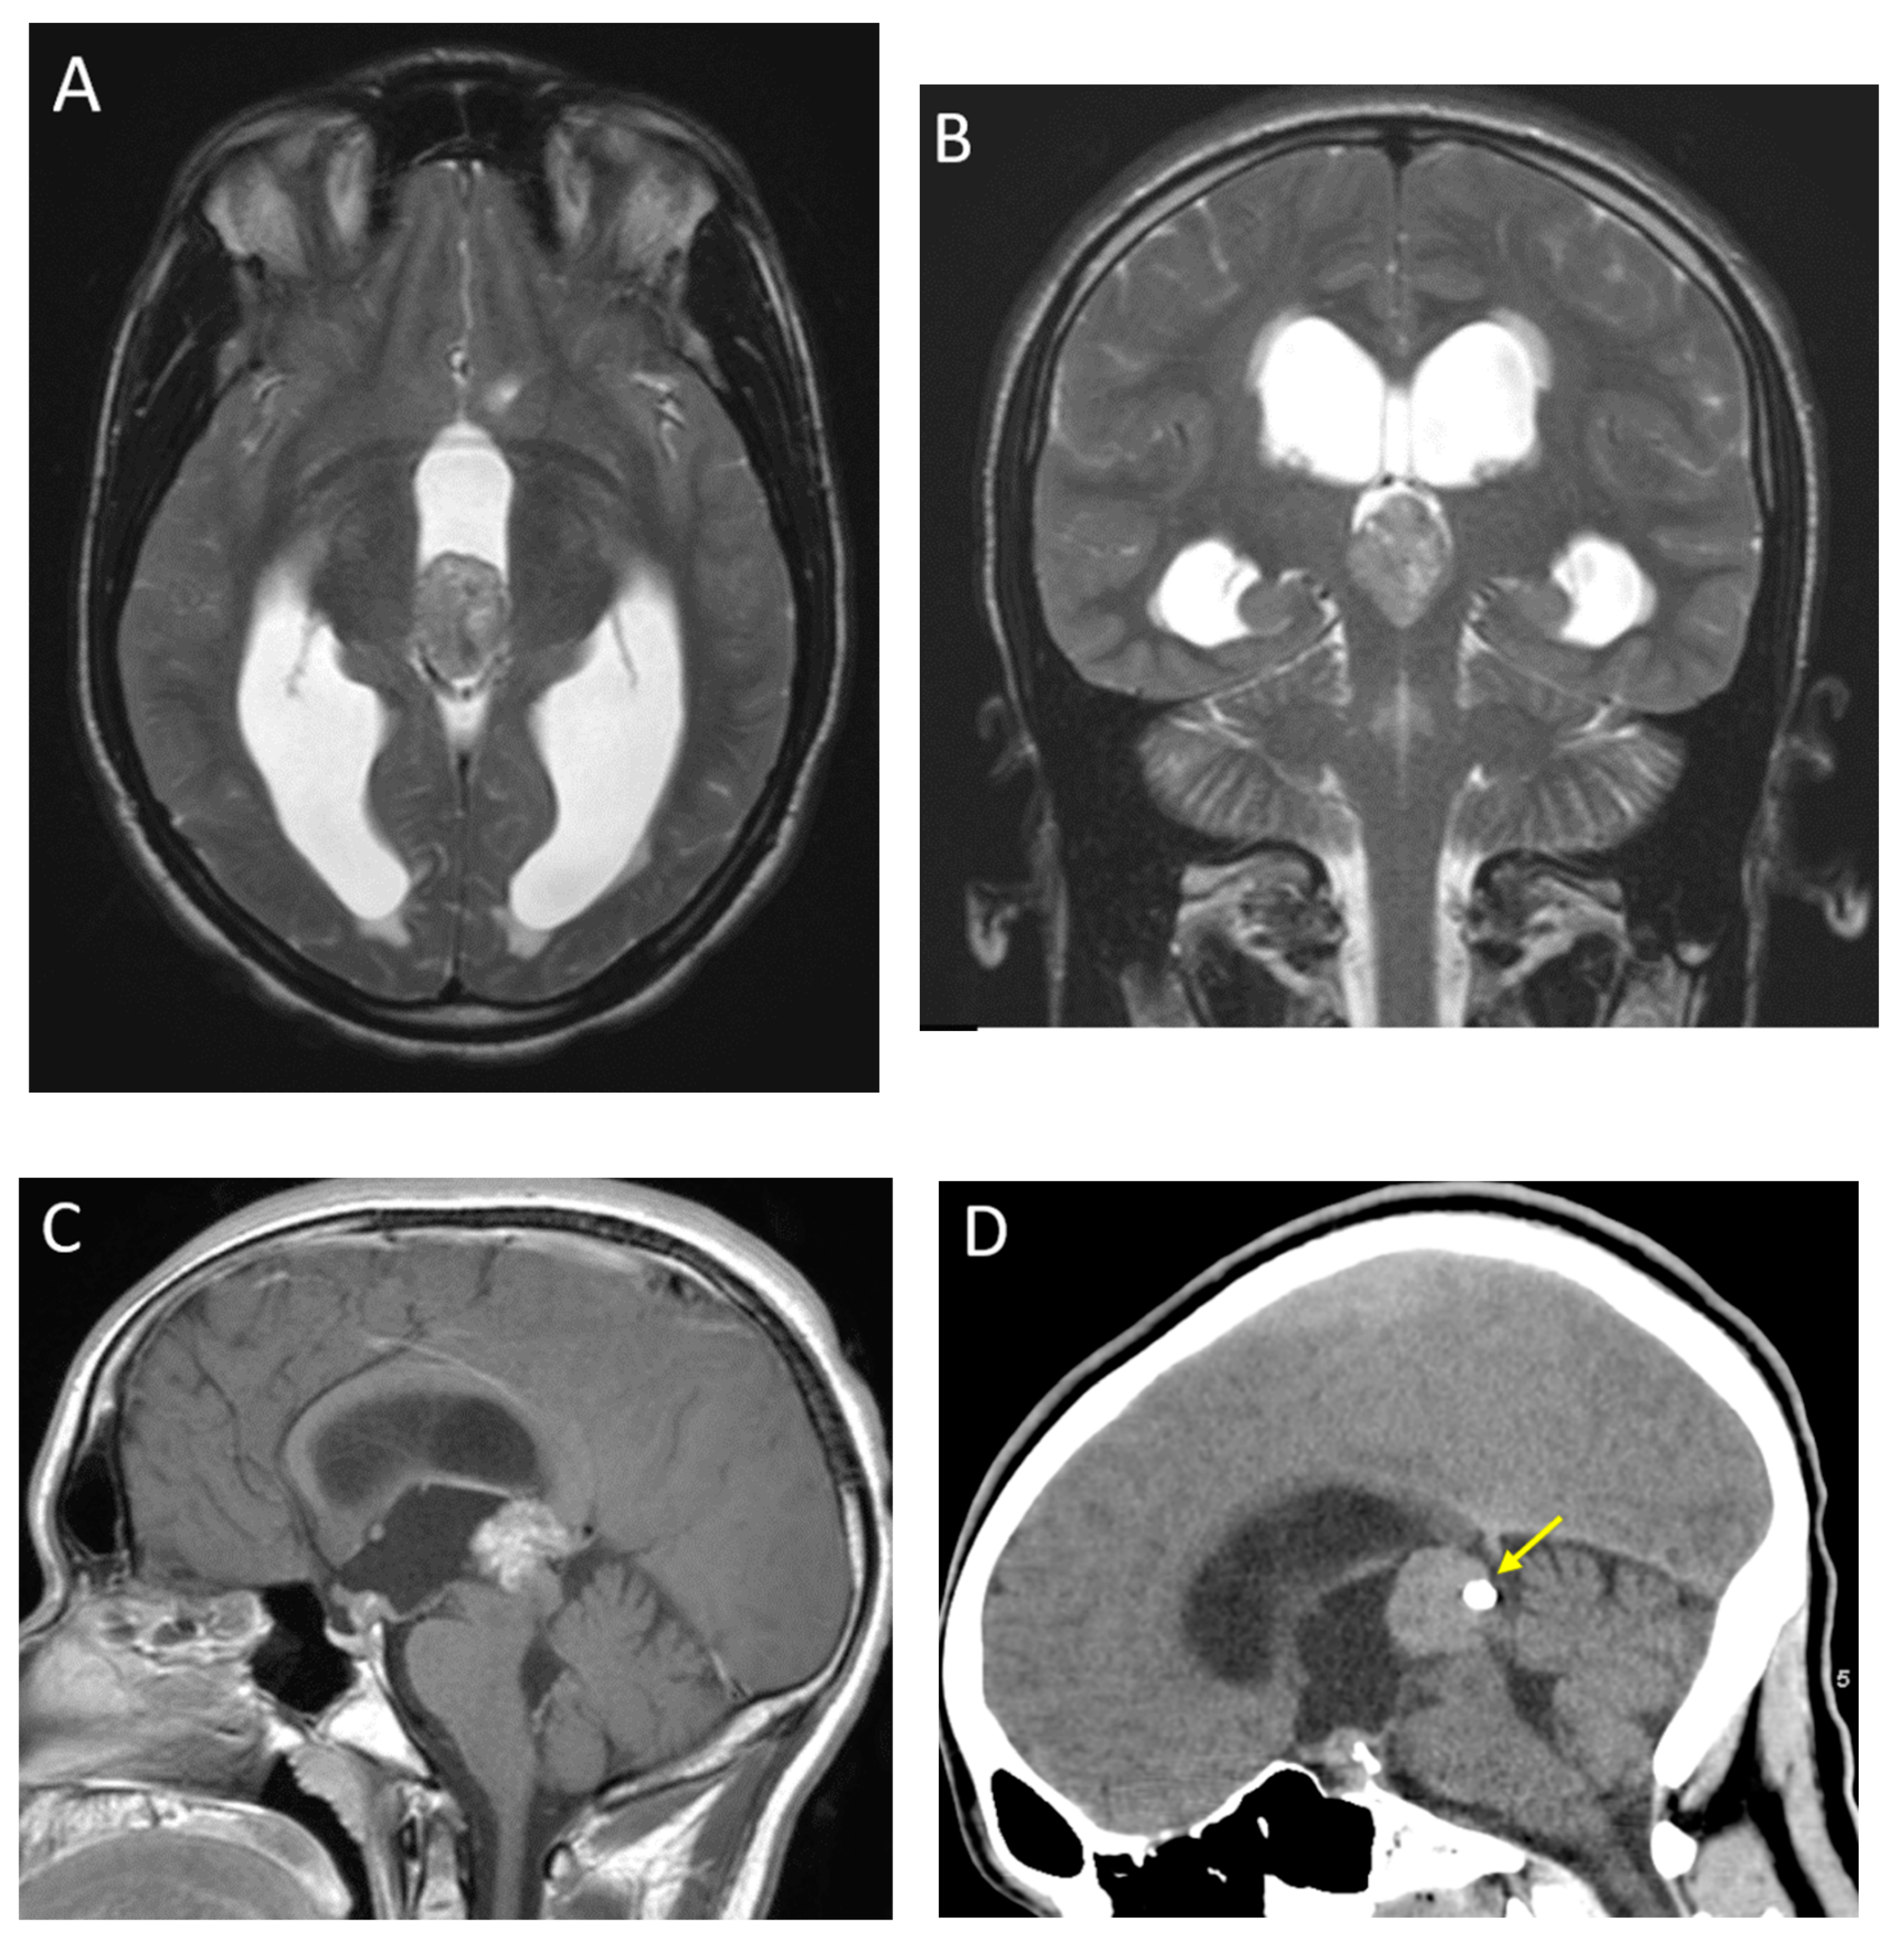

| Diffuse midline glioma (H3K27 altered) | Ventral pons and thalami | Expansile, ill-defined mass No diffusion restriction Usually, non-enhancing at presentation Encasement of basilar artery without narrowing |

| Pilocytic astrocytoma | Cerebellum (most common), brainstem, optic chiasm/hypothalamus | Most commonly, cyst with enhancing mural nodule although cystic component can be variable, and may be completely solid |